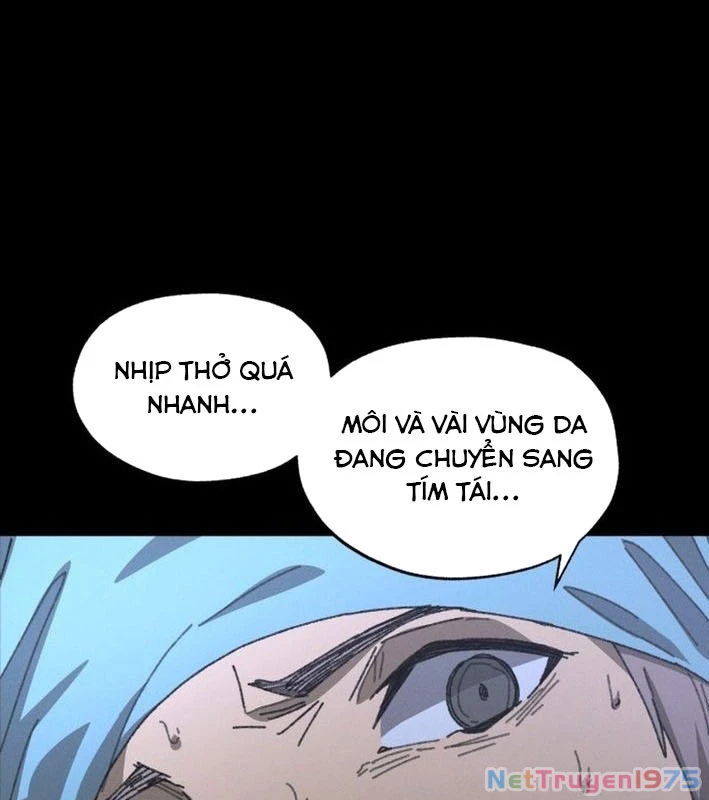

Kẻ Chôn Cất Quái Vật - Chapter 1